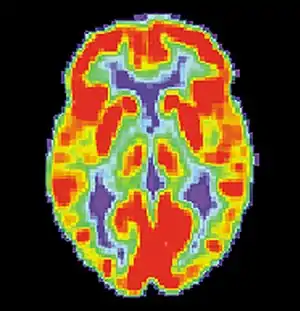

Dopamine

Dopamine Pathways in the brain highlighted in Blue

Dopamine is one of the more known neuromodulators involved in procedural memory. Evidence suggests that it may influence neural plasticity in memory systems by adapting brain processing when the environment is changing and an individual is then forced to make a behavioural choice or series of rapid decisions. It is very important in the process of "adaptive navigation", which serves to help different brain areas respond together during a new situation that has many unknown stimuli and features.[58] Dopamine pathways are dispersed all over the brain and this allows for parallel processing in many structures all at the same time. Currently most research points to the mesocorticolimbic dopamine pathway as the system most related to reward learning and psychological conditioning.[59]